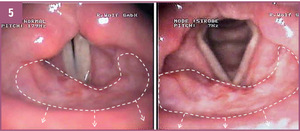

PROF. ADAM MACIEJEWSKI: Pacjenci czują się bardzo dobrze, nie zaobserwowaliśmy żadnych cech nawrotu choroby, co nie zawsze ma miejsce. Operowany przed dwoma laty mężczyzna pod względem jakości życia i funkcjonalności spełnia wszystkie nasze założenia i nadzieje. Nie ma problemów z połykaniem pokarmu, oddychaniem i mową. To było naszym celem, gdyż wiadomo, że nagłośnia jest strukturą, która oddziela drogę oddechową od pokarmowej i warunkuje prawidłowy akt połykania, bez zarzucania treści pokarmowej do dróg oddechowych, co mogłoby skutkować m.in. infekcjami. Prawidłowy przebieg leczenia pooperacyjnego zaobserwowaliśmy także u dwóch pozostałych pacjentów, choć w ich przypadku okres po rekonstrukcji jest krótszy. Warto wspomnieć, że chorzy leczeni tradycyjnymi metodami z powodu raka nagłośni czy raka krtani obejmującego nagłośnię, nawet w przypadku zabiegów oszczędzających, czyli bez usunięcia całej krtani, byli skazani na 80-proc. ryzyko ciężkich powikłań, z 20-proc. ryzykiem zgonu. Tak więc jest to pierwsza w świecie autorska rekonstrukcja, która pozwala na jej odtworzenie i funkcjonalne oddzielenie drogi pokarmowej od oddechowej.

A.M.: Tak, wspólnie uznaliśmy, że opracowanie takiej metody byłoby bardzo skuteczne i pomocne dla cierpiących na średnio lub wysoko zaawansowaną chorobę nowotworową nagłośni lub też średnio zaawansowanego raka krtani obejmującego nagłośnię. Doszliśmy do wniosku, że skoro do tej pory stosowano wiele nieskutecznych metod, nadszedł czas na wykorzystanie trójwymiarowej struktury odpowiadającej nagłośni i pochodzącej z ludzkiego ciała. Założyliśmy więc, że możemy wykorzystać zmodyfikowany fragment małżowiny usznej na naczyniach skroniowych z elementami skóry okolicy przed-, za- i nadusznej. Chodziło nam o to, by te elementy skórne odtwarzały boczne ściany gardła i część górną krtani, która również jest resekowana w przypadku raka nagłośni. Fragment małżowiny usznej z chrząstką w środku mógłby zatem po modyfikacji stanowić element elastyczny odpowiadający kształtowi i wielkości nagłośni. Liczne zabiegi przeprowadzone na zwłokach utwierdziły nas w przekonaniu, że wykonanie takich rekonstrukcji jest możliwe. Po kwalifikacji i przygotowaniu chorych na raka nagłośni w stopniu zaawansowania T2 i T3 z naciekiem na nasadę języka (nie większym niż 1-2 cm, gdzie kończy się możliwość rozsądnej rekonstrukcji), postanowiliśmy wykorzystać tę właśnie technikę.